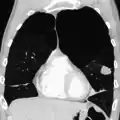

Chest X-ray demonstrating severe COPD: Note the small heart size in comparison to the lungs.

A severe case of bullous emphysema

Axial CT image of the lung of a person with end-stage bullous emphysema

Very severe emphysema with lung cancer on the left (CT scan)